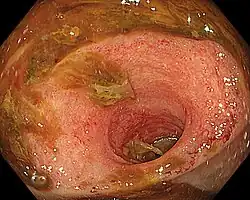

Ileitis caused by capecitabine. | |

Ileitis is an inflammation of the ileum, a portion of the small intestine. Mycobacterium tuberculosis infection may mimic Crohn's disease Ileitis.[1] Ileitis may be linked to a broad range of illnesses, such as sarcoidosis, amyloidosis, ischemia, neoplasms, spondyloarthropathies, vasculitides, drug-related conditions, and eosinophilic enteritis.[2]`